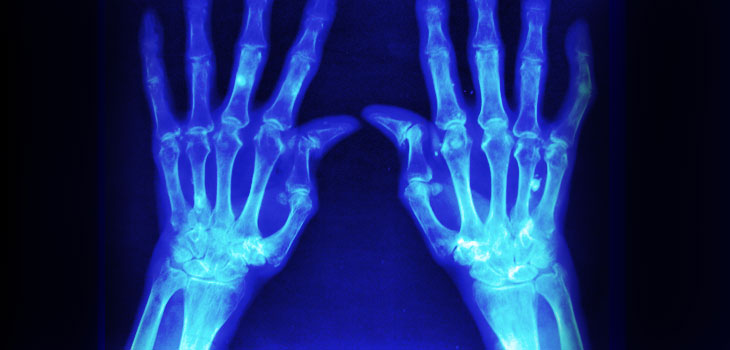

Z tej okazji na portalu społecznościowym Facebook ruszyła akcja pod hasłem rzsporozmawiajmy. Jej celem jest zwiększenie świadomości społeczeństwa na temat reumatoidalnego zapalenia stawów (RZS), którego szczyt zachorowalności przypada na 30 – 40 r.ż., zachęcenie do wykonywania badań diagnostycznych w kierunku RZS oraz zwrócenie uwagi na problem nieprzestrzegania zaleceń terapeutycznych przez pacjentów chorych na RZS.

Reumatoidalne zapalenie stawów